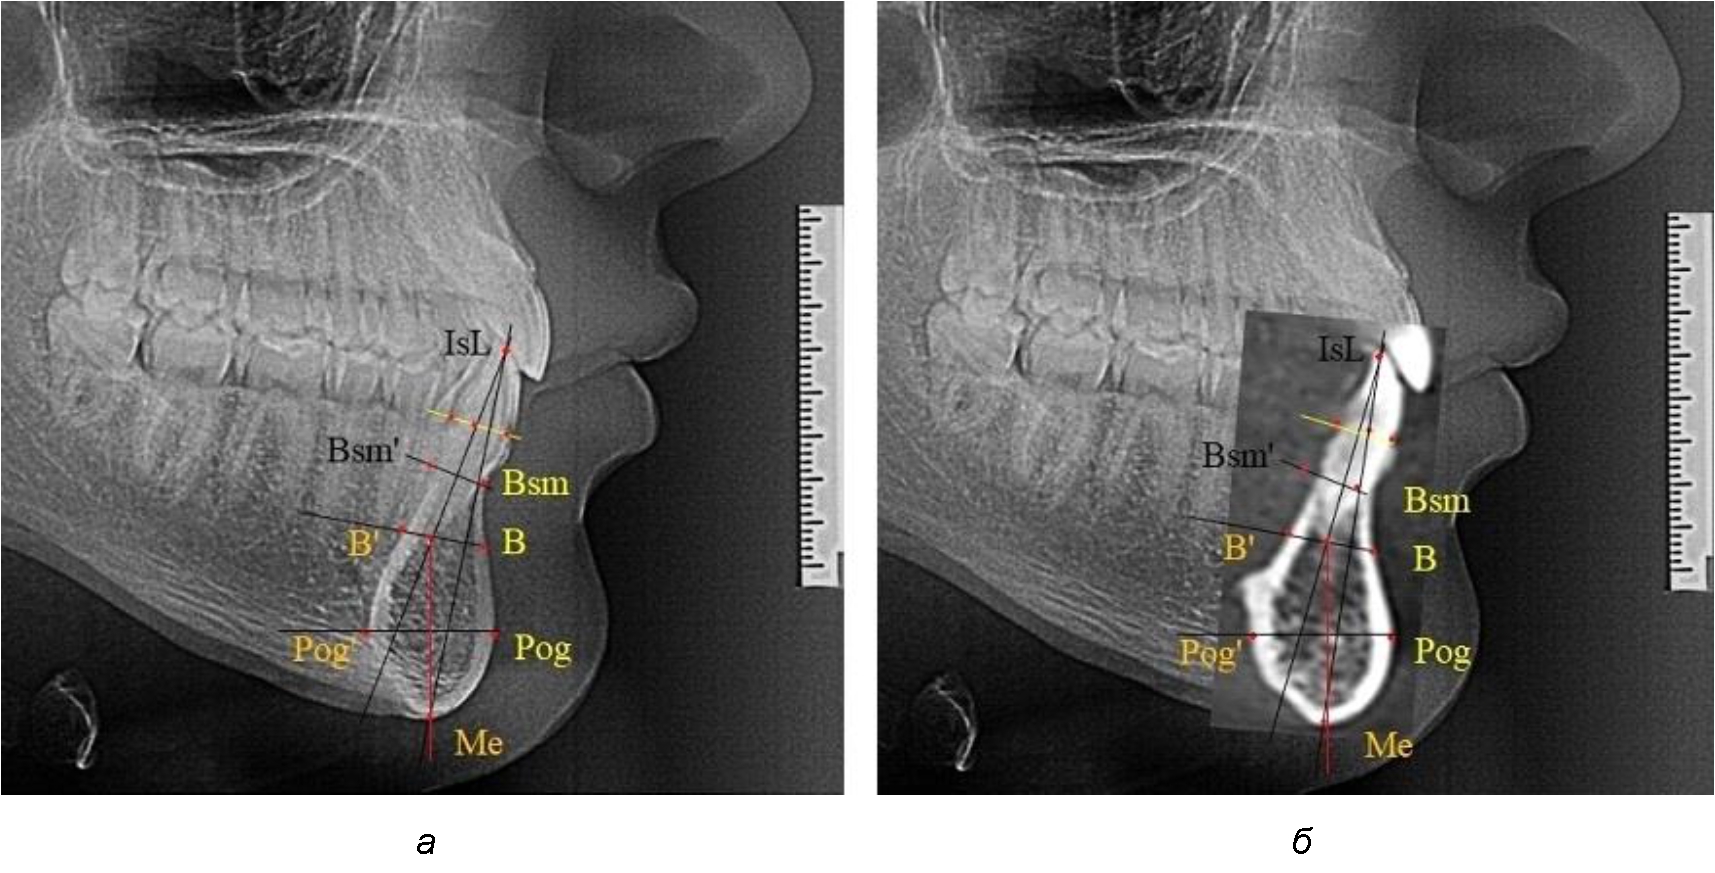

При анализе полученных данных обращает на себя внимание факт того, что из вертикальных параметров зубоальвеолярной части сегмента наиболее вариабельным является размер между апикальными точками Downs и Schwarz (BSM–B), который составлял (6,79 ± 0,54) мм, при величине сигмального отклонения – 2,35. Также большая ошибка репрезентативности и сигмальное отклонение было отмечено при оценки ширины подбородочного выступа. В связи с этим встречались варианты резцовых сегментов нижней челюсти различные как по ширине, так и по высоте, а также по расхождению положения апикальных точек по Downs и Schwarz (рис. 3).

Рис. 3. Варианты среднего (а), широкого (б) и узкого (в) нижнечелюстного резцового сегмента

Типологические варианты подбородочного выступа, различающиеся по ширине, высоте и расположению апикальных точек, необходимо учитывать в клинике ортодонтии при проведении диагностических мероприятий. Протокольные точки для построения эстетических линий, исходящие из выступающей точки подбородка (Рog – погонион), не всегда могут быть объективным критерием диагностики, что объясняется различной выпуклостью переднего отдела подбородочного выступа. Точки апикального базиса по Шварцу и Даунсу находятся в различных местах подбородка и не всегда совпадают, что требует пояснения при выборе ориентиров. Кроме того, вариабельность сагиттальных размеров зубоальвеолярной части резцового сегмента позволит опти-мизировать методы перемещения резцов в переднее-заднем направлении и определяют костный биотип альвеолярной части нижней челюсти в анализируемой области.

При аномалиях окклюзии в сагиттальном направлении и характерных для них различных вариантах протрузионного и/или ретрузионного патологического положения передних зубов, как правило, сопровождается изменениями параметров подбородочного выступа. Учитывая многообразие форм аномалий окклюзии, параметры подбородочного выступа вариабельны как по сагиттали, так и по трансверсали.

Нередко отмечается деформация подбородочного выступа и различное его положение по отношению к зубоальвеолярной части сегмента. При мезиальной окклюзии нередко нижняя подбородочная точка смещается кзади по отношению к условной срединной вертикали нижнего резца, а при дистальной окклюзии отмечается компенсаторное отклонение подбородка кпереди (рис. 5).

Рис. 5. Особенности нижнечелюстного резцового сегмента на ТРГ у людей при мезиальной (а) и дистальной (б) окклюзии

Кроме того, так же как и у людей с физиологической окклюзией, определялось различие в положении апикальных точек Downs и Schwarz, что, по нашему мнению, может определять тактику лечения патологических форм протрузии/ретрузии резцов с учетом биотипа костной ткани.